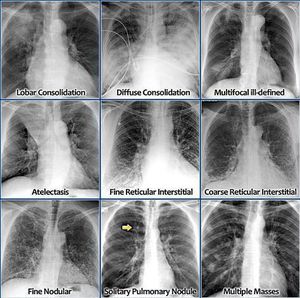

Multiplemasses

Solitarypulmonarynodule

Finenodular